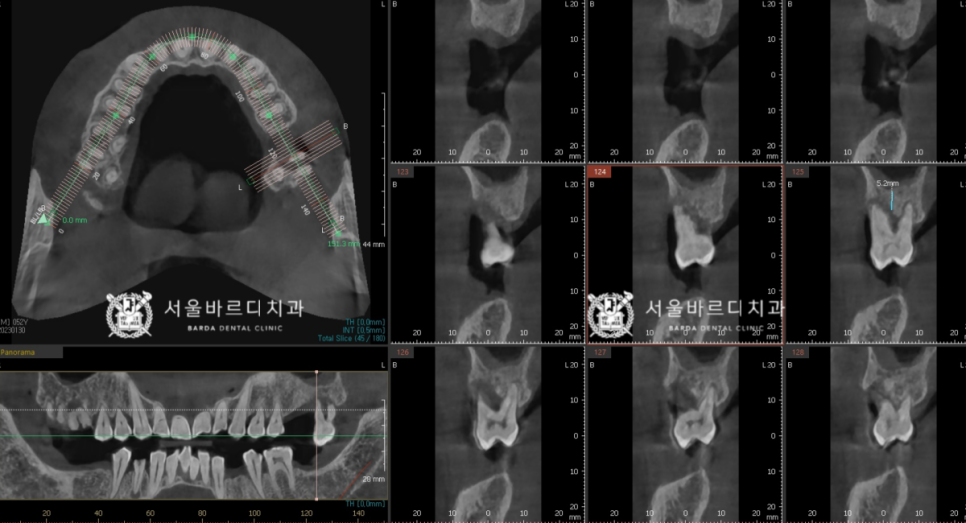

술전에는 3D CT와 구강 스캔 데이터를 가지고,

모의 수술을 해 본 후에 시뮬레이션 결과대로

식립할 수 있게 하는 가이드 장치를 제작합니다.

맞춤 장치를 제작하여 적용하는 방식을

네비게(개)이션 임플란트라고 하는데요.

저희는 디지털 기술을 적극 도입하여

뼈 상태가 좋은 자리에 해부학적 구조물을 피해서

안전하게 시술하고 있습니다.